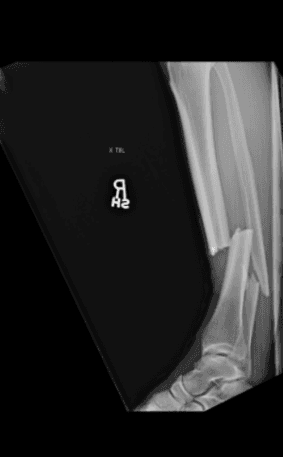

Así quedó la pierna tras la patada. Foto: Twitter